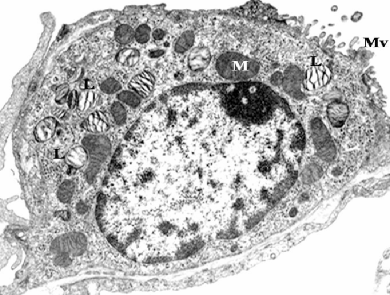

Type II pneumocyte

Identify labeled cell, sites and one specific feature?

Clara cell , mucosa of bronchiole, dome shaped apical surface and secretory granules

A -Identify the cell

B -Identify the labelled structure

A- pneumocyte type II

B- Lamellar bodies